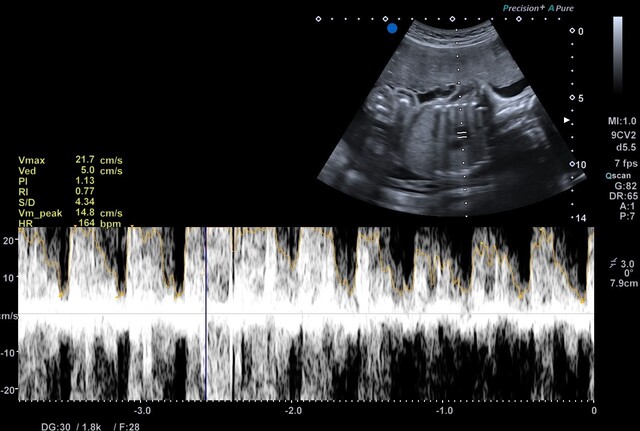

Umbilical cord

Check cord insertion, position, and presence of nuchal cord (cord around the neck).